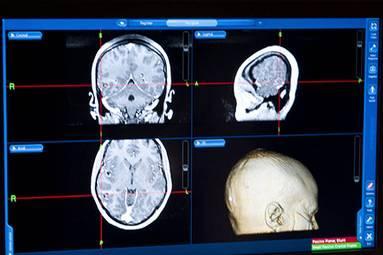

El Hospital Memorial Hermann, en la ciudad de Houston, en EEUU, trasmitió una cirugía de cerebro en Twitter, Youtube y la red social Pinerest. El paso a paso de la extracción de un tumor, que duró más de tres horas, pudo seguirse en tiempo real, mediante imágenes y videos.

El neurocirujano a cargo de la operación fue el doctor Dong Kim, famoso por haber atendido a la ex congresista Gabrielle Giffords después de haber recibido un disparo en la cabeza en enero de 2011.